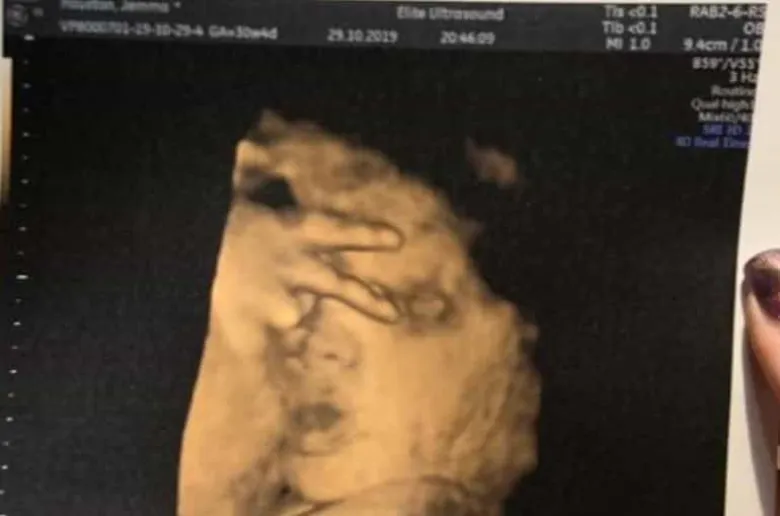

Դեռ չծնված երեխան ուլտրաձայնային հետազոտության ժամանակ հաղթանակի՝ «V» նշանն է ցույց տվել՝ ապշեցնելով բժիշկներին

Չծնված երեխան ուլտրաձայնային հետազոտության ժամանակ հաղթանակի՝ «V» նշանն է ցույց տվել՝ ծիծաղեցնելով ծնողներին և ապշեցնելով բժիշկներին, գրում է The Sun-ը:

Շոտլանդիայի Փեյսլի քաղաքի բնակչուհի Ջեմմա Հյուսթոնը պատմել է, որ ուլտրաձայնային հետազոտության ժամանակ իր ապագա երեխան ապշեցրել է բժիշկներին՝ ցույց տալով հաղթանակի «V» նշանը: Հյուսթոնը նշել է, որ իր դուստրն ուլտրաձայնային հետազոտությունների ժամանակ երբեք չի «օգնում» և ճիշտ դիրքում երբեք չի հայտնվում:

Հղի կինը հայտնել է, որ արդեն 4 ուլտրաձայնային հետազոտություն է անցել, սակայն երեխային հստակ ցույց տվող ոչ մի լուսանկար չունի:

Նա հավելել է, որ դուստրն իսկական «դիվա» է լինելու և մորից ժառանգելու է նրա հատկանիշները: Հյուսթոնն ասել է, որ դստեր վարքագիծը շատ ծիծաղելի էր, և նրա լուսանկարն ապագայում անպայման ցույց է տալու նրան: